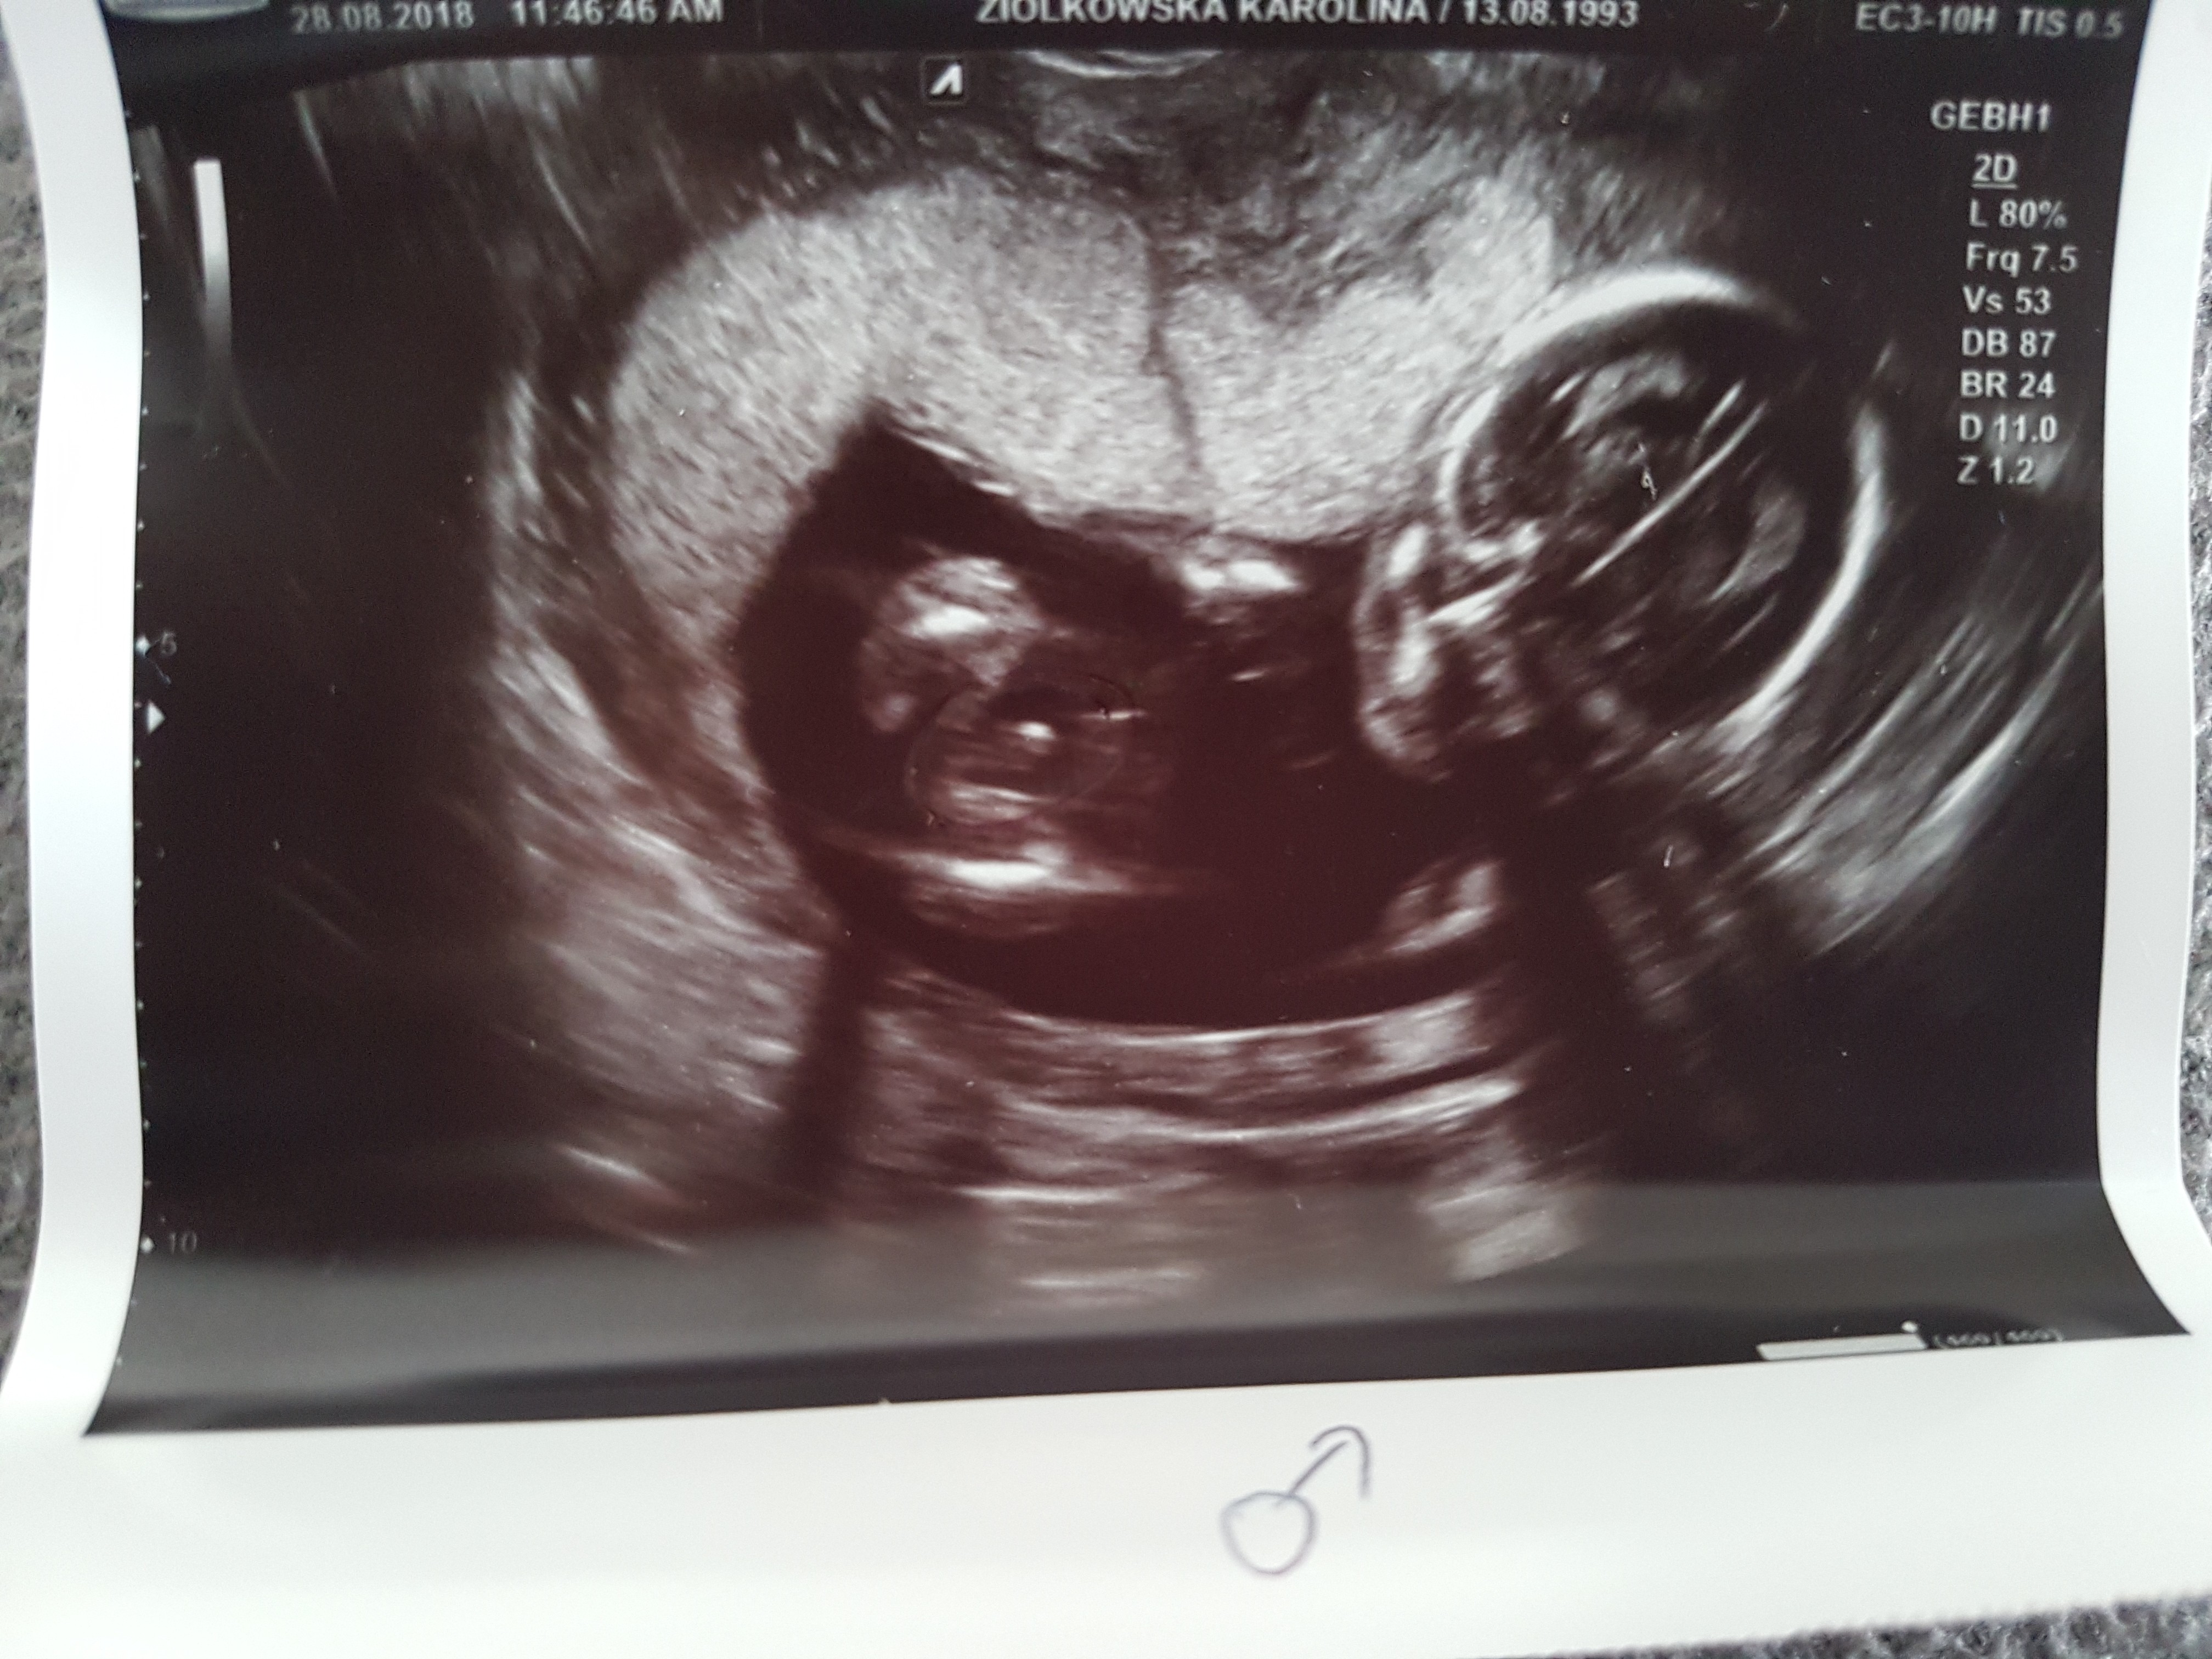

Mi pani doktor na badaniach prenatalnych w 12 tygodniu ciąży z niepewną miną powiedziała że będzie dziewczynka, potwierdziła to 8 tygodni później na badaniach połówkowych, a w 31 Tc byłam na usg 3D i mam tak zwane czarno na białym [emoji5] [emoji14]

IMG_20180730_114814.jpg

• IMG_20180730_114814.jpg

49,6 KB · Wyświetleń: 1 929